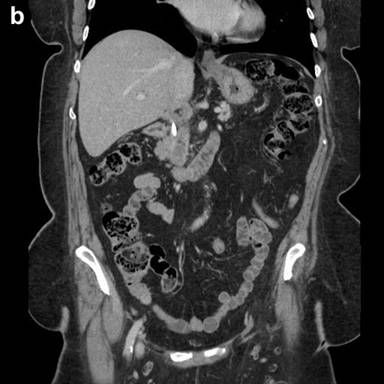

Microscopy revealed that the main bulk of the tumor was cystic/hemorrhagic and located within the uncinate process. At the same time, the tumor was intimately related to the main pancreatic duct and its branches. It grew along their lumen as an intraductal, pencil like growth and protruded into the lumen of the duodenum, forming a polypoid structure. Both components (cystic and intraductal) were predominantly comprised of non-epithelial component: pleomorphic large cells, histiocyte-like mononuclear cells, atypical mononuclear cells and spindle cells with multiple, atypical and bizarre mitoses, as well as osteoclast-like giant cells (Figure 3a). Extensive sampling of the tumor revealed a minor epithelial component (Figure 3bcd), showing glandular differentiation within the intraductal pencil-like growth present in the main pancreatic duct and its branches (Figure 3ef), as well within the cystic component.

Figure 3. Histomorphologic findings. a. Mixture of the pleomorphic large cells, histiocyte-like mononuclear cells, atypical mononuclear cells and osteoclast-like giant cells (H&E, original magnification 20x). b. As above, but mixed with epithelial neoplastic cells (H&E, original magnification 20x). c. and d. Epithelial neoplastic cells strongly positive for pankeratin and cytokeratin 34 beta E12 (original magnification 20x). e. Early intraductal growth of the undifferentiated carcinoma of the pancreas (H&E, original magnification 2x). f. Pancreatic duct almost completely occluded by intraductal growth of the undifferentiated carcinoma of the pancreas (H&E, original magnification 2x). |